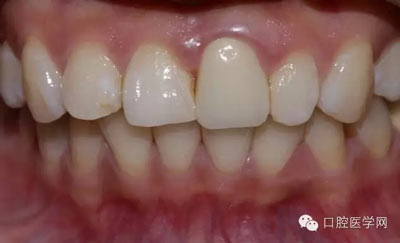

術(shù)前照

檢查:21金屬烤瓷冠修復(fù),顏色及形態(tài)與鄰牙不協(xié)調(diào),牙齦有輕微發(fā)黑,扣痛(-)、松動度(-);11近中鄰面齲壞